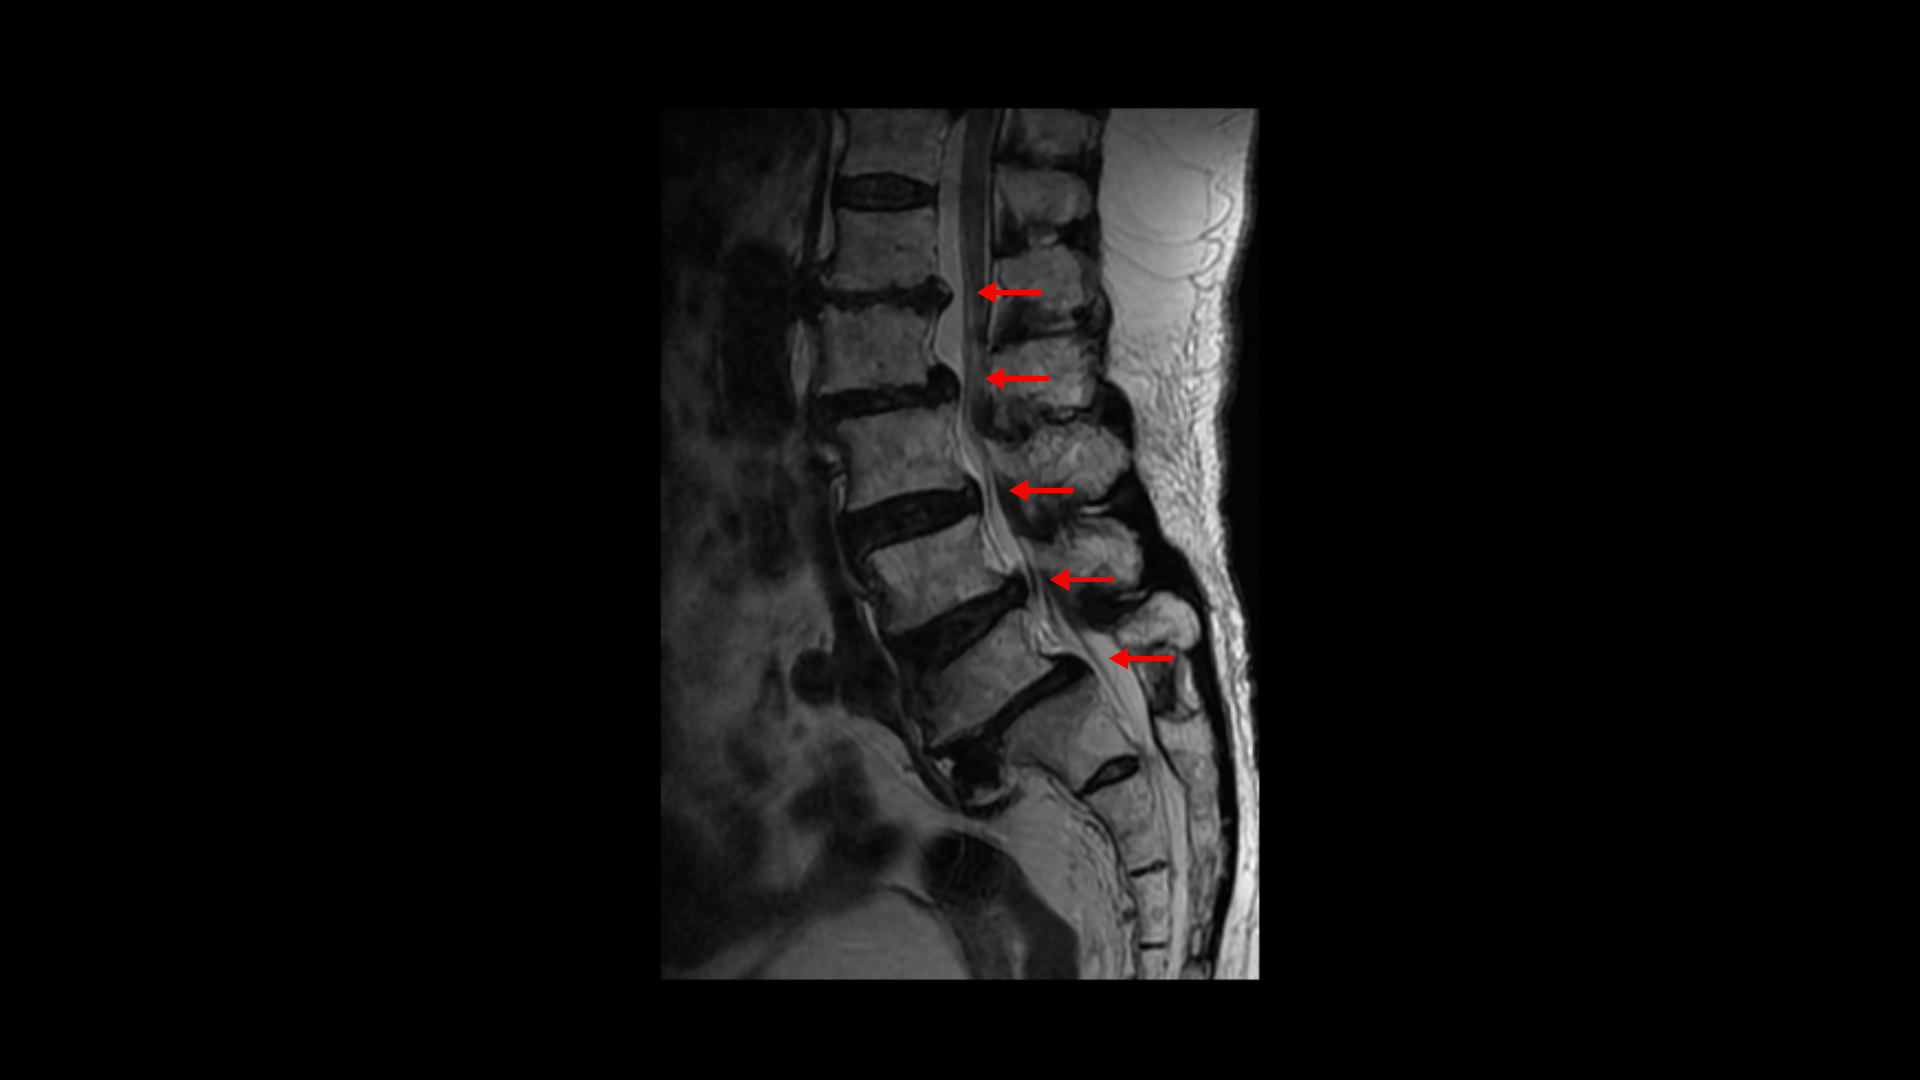

이분 MRI를 보면 보시다시피 허리의 5마디가 전부 퇴행이 진행되어 있습니다.

우선 전방전위가 2마디에 있고

여러 마디 2번 3번, 4번 5번에 척추관협착이 있고

2번 3번, 4번 5번, 오른쪽 신경가지가 빠져나가는 구멍들이 다섯 마디 전부가 다 오른쪽 좁아져 있습니다.

그런데 이분은 허리도 굽으셨는데 척추근육, 특히 허리를 세워주는 기립근을 mri에서 보면 허리 다섯 마디 전체에서 기립근의 근육이 지방으로 변해서 하얗게 보이는 지방화가 심합니다.

이렇게 근육이 지방으로 심하게 변하고 기능이 떨어지면 허리를 펴기가 어렵고 허리가 아플 수 밖에 없습니다. 여기 건강한 기립근과 비교해서 보면 그 차이를 금방 알 수가 있습니다. 기립근 크기도 차이가 크고 하얗게 지방으로 변해버린 부분을 잘 보실 수 있습니다.